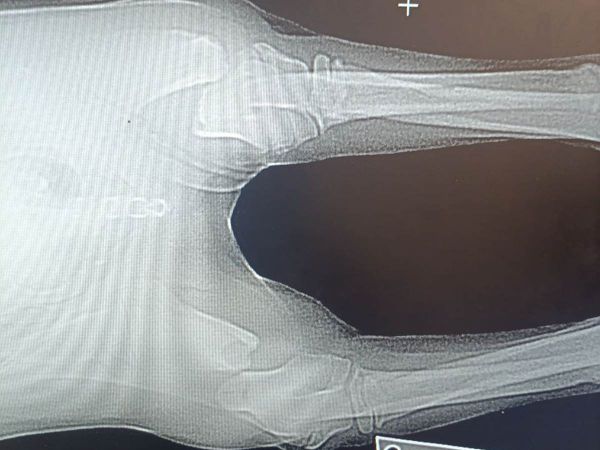

Нашли собачку, ориентировочно, 19 сентября. Пес лежал совершенно без движения, у него были серьезные переломы передних лап. Судя по травмам, волонтеры предполагают, что его выбросили из машины на полном ходу.

– Только так мы можем объяснить такие дикие и параллельные переломы на обеих передних лапках, – говорит Ольга.